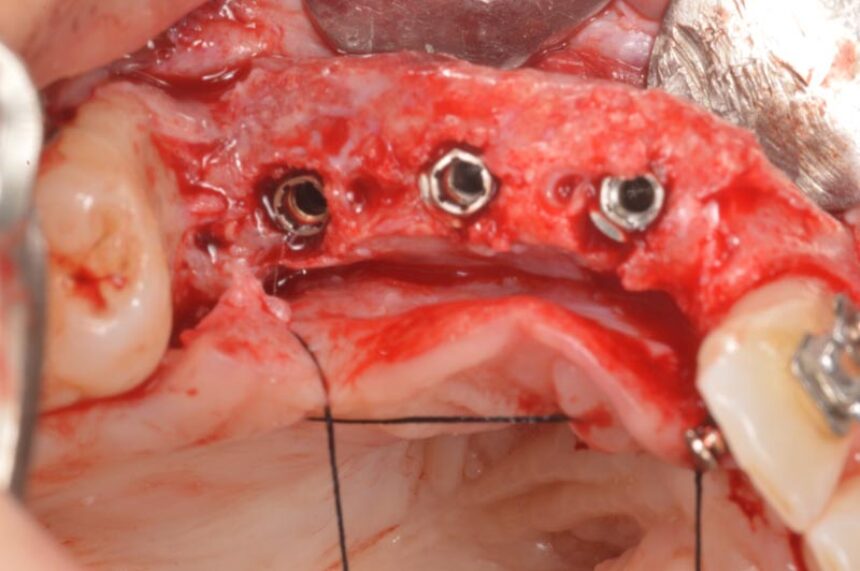

Οριζόντια και Κάθετη Αύξηση της Ακρολοφίας: χειρουργικό υπόβαθρο - χειρουργικές τεχνικές – απορροφήσιμες και μη-απορροφήσιμες μεμβράνες – λήψη οστικού μοσχεύματος από ενδο-στοματικά σημεία – βίντεο